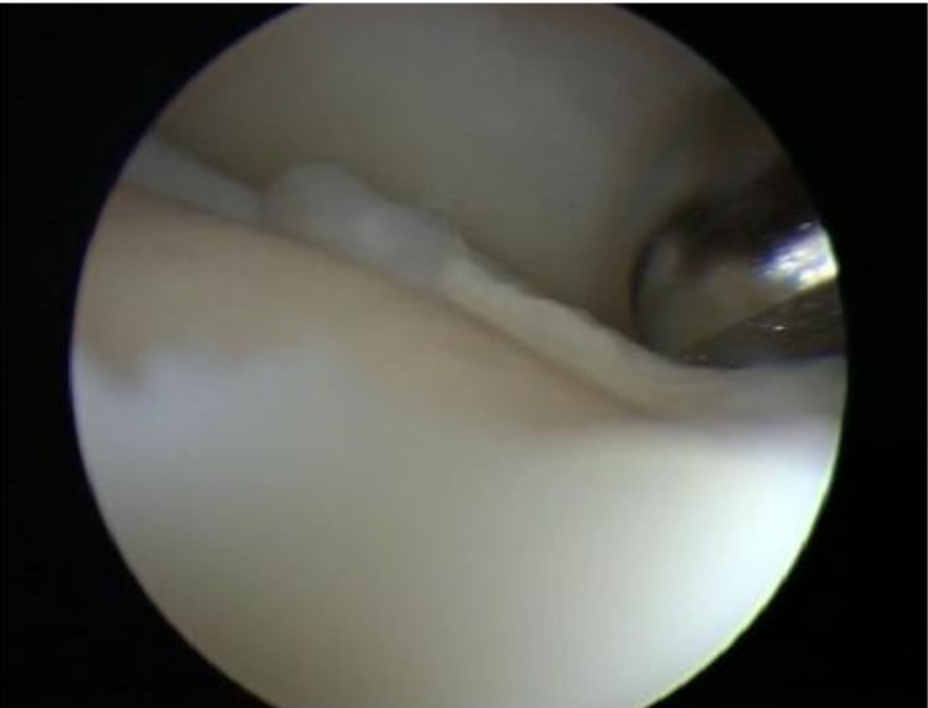

软骨成形术使用踝关节前侧关节镜标准入路,插入 2.3 或 2.7mm 镜头和探钩,检查软骨表面不规则处,区分软化 / 不稳定软骨(可能伴撕裂)与健康软骨。用刨刀(2.2、3.5 或 4.2mm)打磨纤维化软骨,注意保护周围健康组织。通过刨刀打磨软骨表面,平整粗糙面,避免软骨碎片脱落形成游离体影响关节活动,同时切除表面裂纹以减少损伤加深,通过消除不平整改善关节内负荷分布。